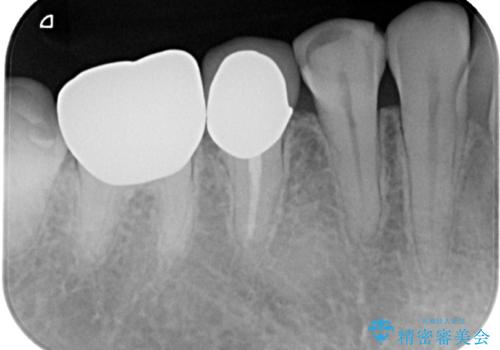

検診で見つかった齲蝕のセラミックインレー修復

- 検診で初期の齲蝕が見つかった患者様です。

これ以上神経の治療や被せものになりたくないため、初期のうちにしっかりとした治療をしたいとのことでした。

齲蝕をしっかりと除去して、精度の高いシリコーンによる型どりを行いセラミックインレーで修復しました。

精度の高い治療は再度齲蝕になるリスクが低いです。